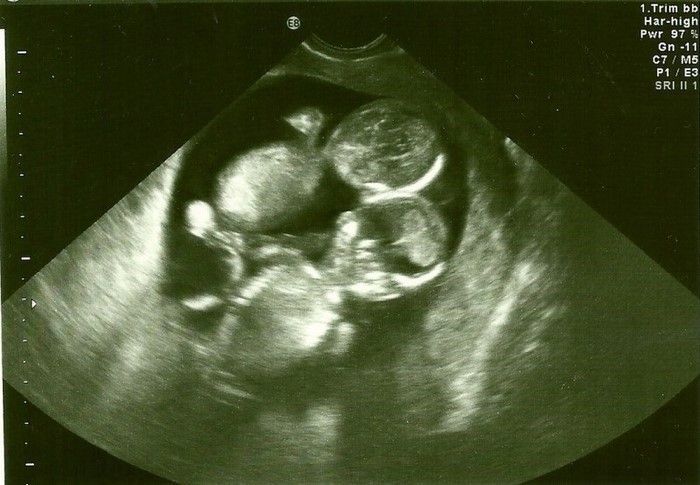

A la 10 ª semana de embarazo, después de sufrir un severo resfriado, la mujer llegó a la consulta unos días antes de la fecha programada. Allí se enteró de que esperaba no uno, sino a dos bebés a la vez. Sin embargo, ¡las siguientes palabras del médico dejaron a Kate en estado de shock!

Los niños que estaban en el vientre de la futura madre, eran gemelos monoamnióticos. Entre estos bebés en el saco amniótico no hay separación alguna, por lo que la probabilidad de que el cordón umbilical se enrede, aumenta en veces. Además, en la última etapa del embarazo, los cordónes umbilicales pueden enredarse de la peor manera, representando un riesgo significativo de asfixia para uno o ambos bebés.

Kate y su marido encontraron a los mejores especialistas y siguieron sus recomendaciones. Primero, la mujer debía realizar el ultrasonido cada dos semanas. Después de la semana 24 ª de embarazo, las ecografías pasaron a ser semanales.